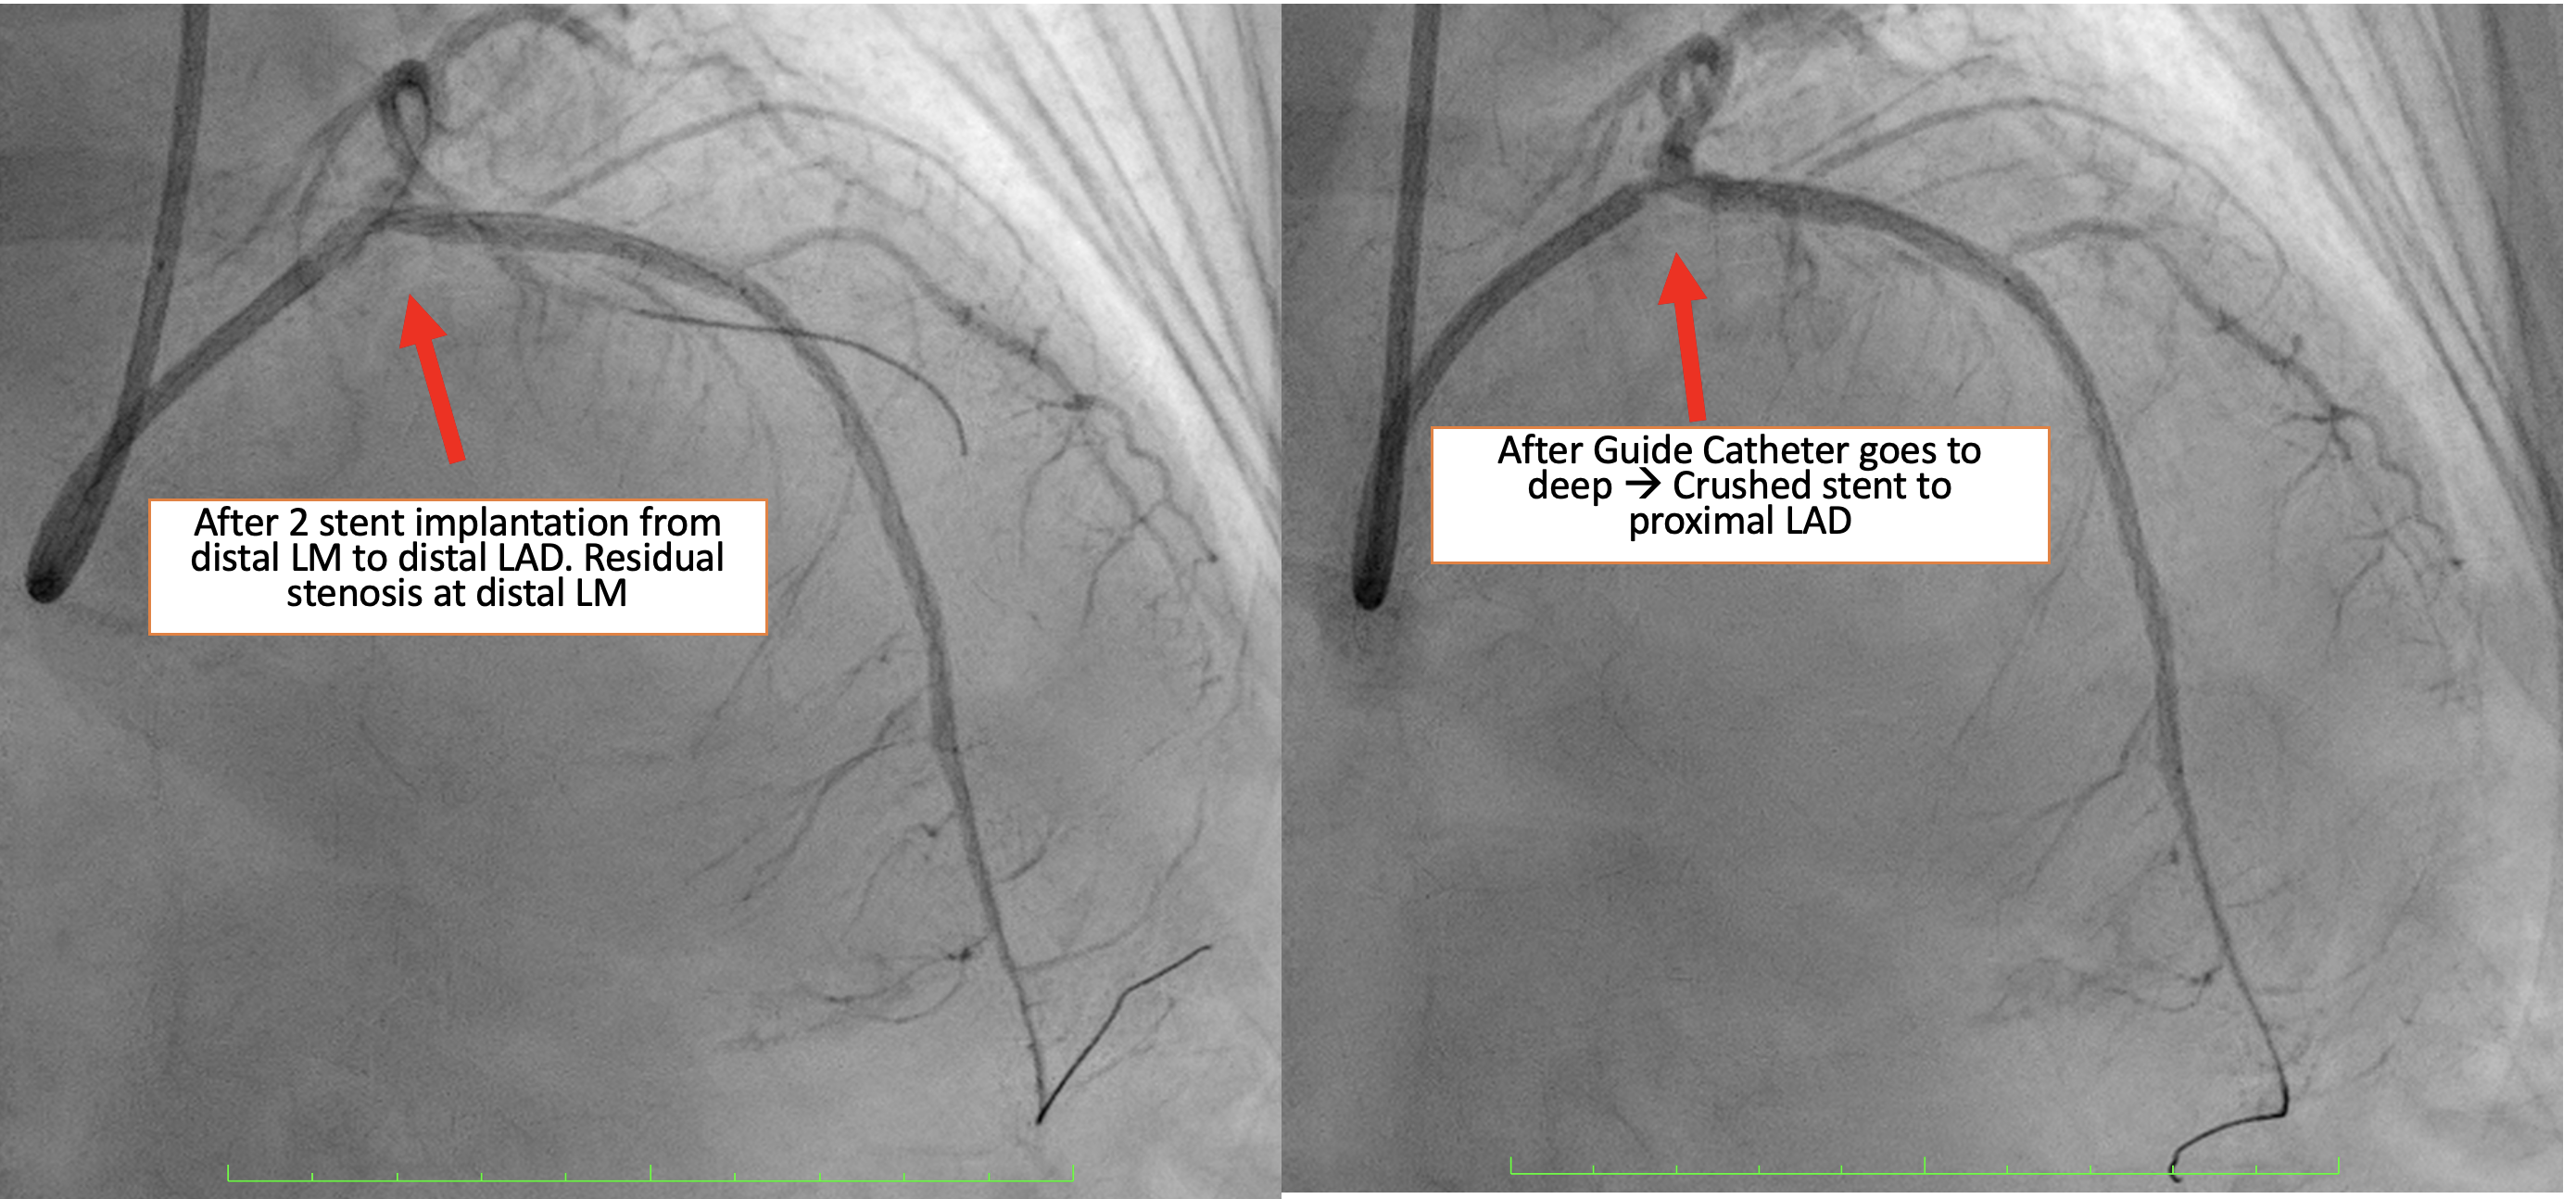

Procedural Step

Based on angiographic and IVUS findings, the lesion was prepared using a scoring non-compliant (NC) balloon (ScoreFlex) 2.5 mm ¡¿ 15 mm, inflated from the distal LAD to distal LM at a maximum of 18 atm. A first drug-eluting stent (DES) Cre8 2.75 mm ¡¿ 46 mm was deployed from the proximal to distal LAD, followed by a second DES (Combo Plus) 3.5 mm¡¿ 38 mm from the distal LM to the proximal LAD with overlap. During withdrawal of the stent balloon, the guiding catheter (XB 3.5/ 7 Fr) advanced too deeply, resulting in crushing of the proximal portion of the Combo Plus stent. Angiography showed that the crushed stent no longer adequately covered the distal LM lesion. Attempts were made to reopen the crushed segment using a series of semi-compliant balloons (Sapphire II Pro): 0.85 mm ¡¿ 15 mm, 1.0 mm ¡¿ 15 mm, and 2.0 mm ¡¿ 15 mm, each inflated to a maximum 20 atm. A non-compliant (NC) balloon 4.5 mm ¡¿ 8 mm was then used to dilate the stent struts. A third DES (Ultimaster Tansei) 3.5 x 24 mm was deployed from the ostial LM to the proximal LAD, overlapping the previously crushed stent. Proximal optimization (POT) was performed in the LM using a 4.5 mm ¡¿ 8 mm NC balloon inflated to 22 atm. Final angiography showed a satisfactory result with minimal residual stenosis in the distal LM. The final IVUS assessment could not be perfromed due to damage to the IVUS catheter

Case Summary

Careful manipulation of the guiding catheter is essential, especially during balloon withdrawal from complex or calcified lesions. Maintaining wire position within the true stent lumen is crucial for successfully reopening or reconstructing a crushed stent and ensuring optimal procedural outcomes.